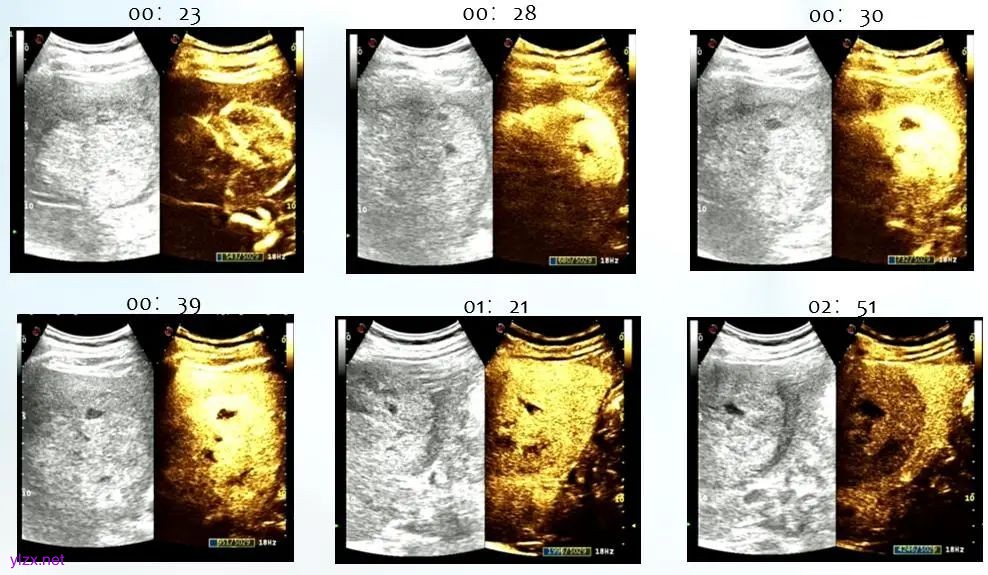

图2. 超声造影声像特征

肝脏穿刺活检病理: